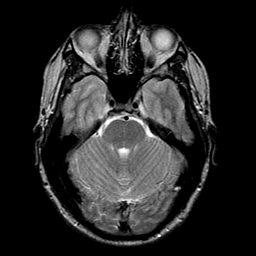

glioma overlay -- Slice #8

[Home][Help][Clinical] Slice 8